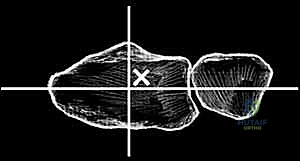

The proximal row of the carpus (scaphoid, lunate, triquetrum) articulates with the distal radius to form the radiocarpal joint, functioning largely as an intercalated segment whose motion is dictated by the surrounding osseous contours and ligamentous tethers. The distal carpal row articulations with the metacarpal bases form the relatively rigid CMC joints. Within the distal carpal row, the primary center of wrist motion is located at the head of the capitate, slightly palmar to the geometric center of the head. This center of rotation may or may not be perfectly colinear with the third metacarpal shaft, depending on the unique anatomic variance of each patient. Proximally, the center of wrist motion lies slightly ulnar to the central axis of the radial intramedullary canal.

Imaging studies are critical for both diagnosis and templating. Standard posteroanterior (PA), lateral, and oblique wrist radiographs provide sufficient imaging for the vast majority of preoperative planning. In cases of severe deformity, prior trauma, or suspected massive bone loss, a non-contrast computed tomography (CT) scan with 3D reconstructions is highly recommended to assess the precise geometry of the distal radius and the integrity of the capitate and metacarpal bases. Digital or acetate templating is utilized to determine the appropriate size for the radial body and stem, the capitate stem, the carpal plate and body, the scaphoid augment (if utilized), and the lengths of the radial and ulnar fixation screws.

Carpal preparation requires exacting precision. Using the Maestro system as the archetype, the carpal resection guide is positioned to allow resection of 2 to 3 mm of the capitate head. It is provisionally held in position with two 0.062-inch Kirschner wires. The first wire is placed into the capitate neck and the second into the metaphysis of the third metacarpal, ensuring that the guide is perfectly parallel to the third metacarpal axis. With proper placement, the ulnar guide wing will lie close to the triquetrum–hamate articulation, and the radial wing will bisect the scaphoid at its distal third.